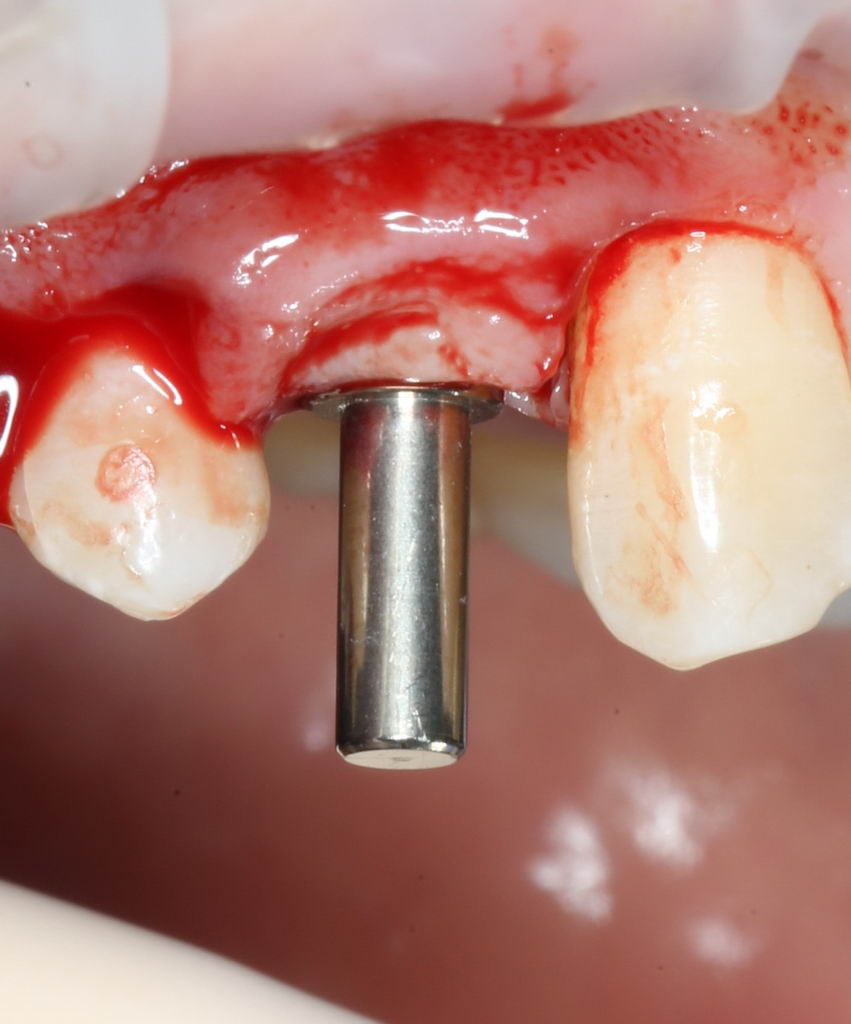

Еще раз проверим положение имплантата:

Учитывая то, что на нём уже установлен временный абатмент TempBase, сделать это очень просто. Фактически, сейчас мы с Вами видим картинку, которую увидит ортопед перед установкой коронки. Это очень удобно.

Больше нам абатмент TempBase не нужен, мы его убираем:

Без абатмента можно оценить позиционирование имплантата по глубине погружения. Напомню, что XiVE — это субгингивальная имплантационная система, поэтому ортопедическая платформа имплантата должна находиться на уровне костной ткани. Что и было выполнено в нашем случае.

И, коль всё в порядке, переходим к следующему этапу операции — установке формирователя десны.